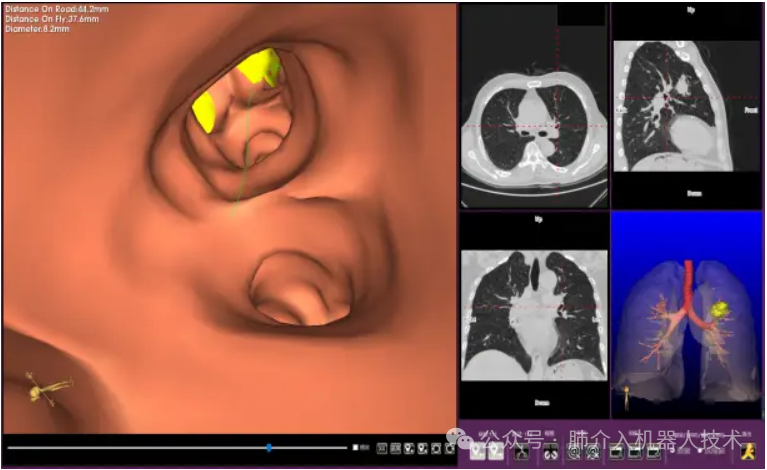

03、奧泰康助力肺部穿刺手術(shù)導(dǎo)航系統(tǒng)獲證

2024年1月31日,經(jīng)國(guó)家藥品監(jiān)督管理局公示,蘇州朗開醫(yī)療技術(shù)有限公司自主研發(fā)的肺部穿刺手術(shù)導(dǎo)航系統(tǒng)(國(guó)械注準(zhǔn)20243010222)獲得NMPA批準(zhǔn)上市,奧泰康助力本項(xiàng)目注冊(cè)申報(bào)服務(wù),系2024年奧泰康助力獲得的首張三類醫(yī)療器械注冊(cè)證。

25、醫(yī)達(dá)健康IQQA®極星干將™2號(hào)Robot智能穿刺導(dǎo)航定位機(jī)器人獲批上市

2024年8月,由醫(yī)達(dá)健康自主創(chuàng)新研發(fā)的IQQA®極星干將™2號(hào)Robot智能穿刺導(dǎo)航定位機(jī)器人通過(guò)國(guó)家藥品監(jiān)督管理局(NMPA)注冊(cè)審核,并獲得第三類醫(yī)療器械注冊(cè)證,奧泰康負(fù)責(zé)臨床試驗(yàn)服務(wù)。